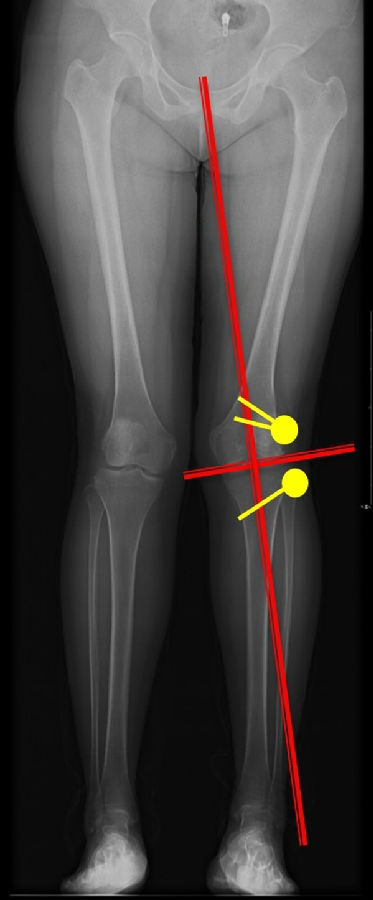

步骤四:确定合页位置和截骨线方向

此患者计划股骨内侧闭合楔,胫骨内侧开放楔。

步骤五:Miniaci法测量角度